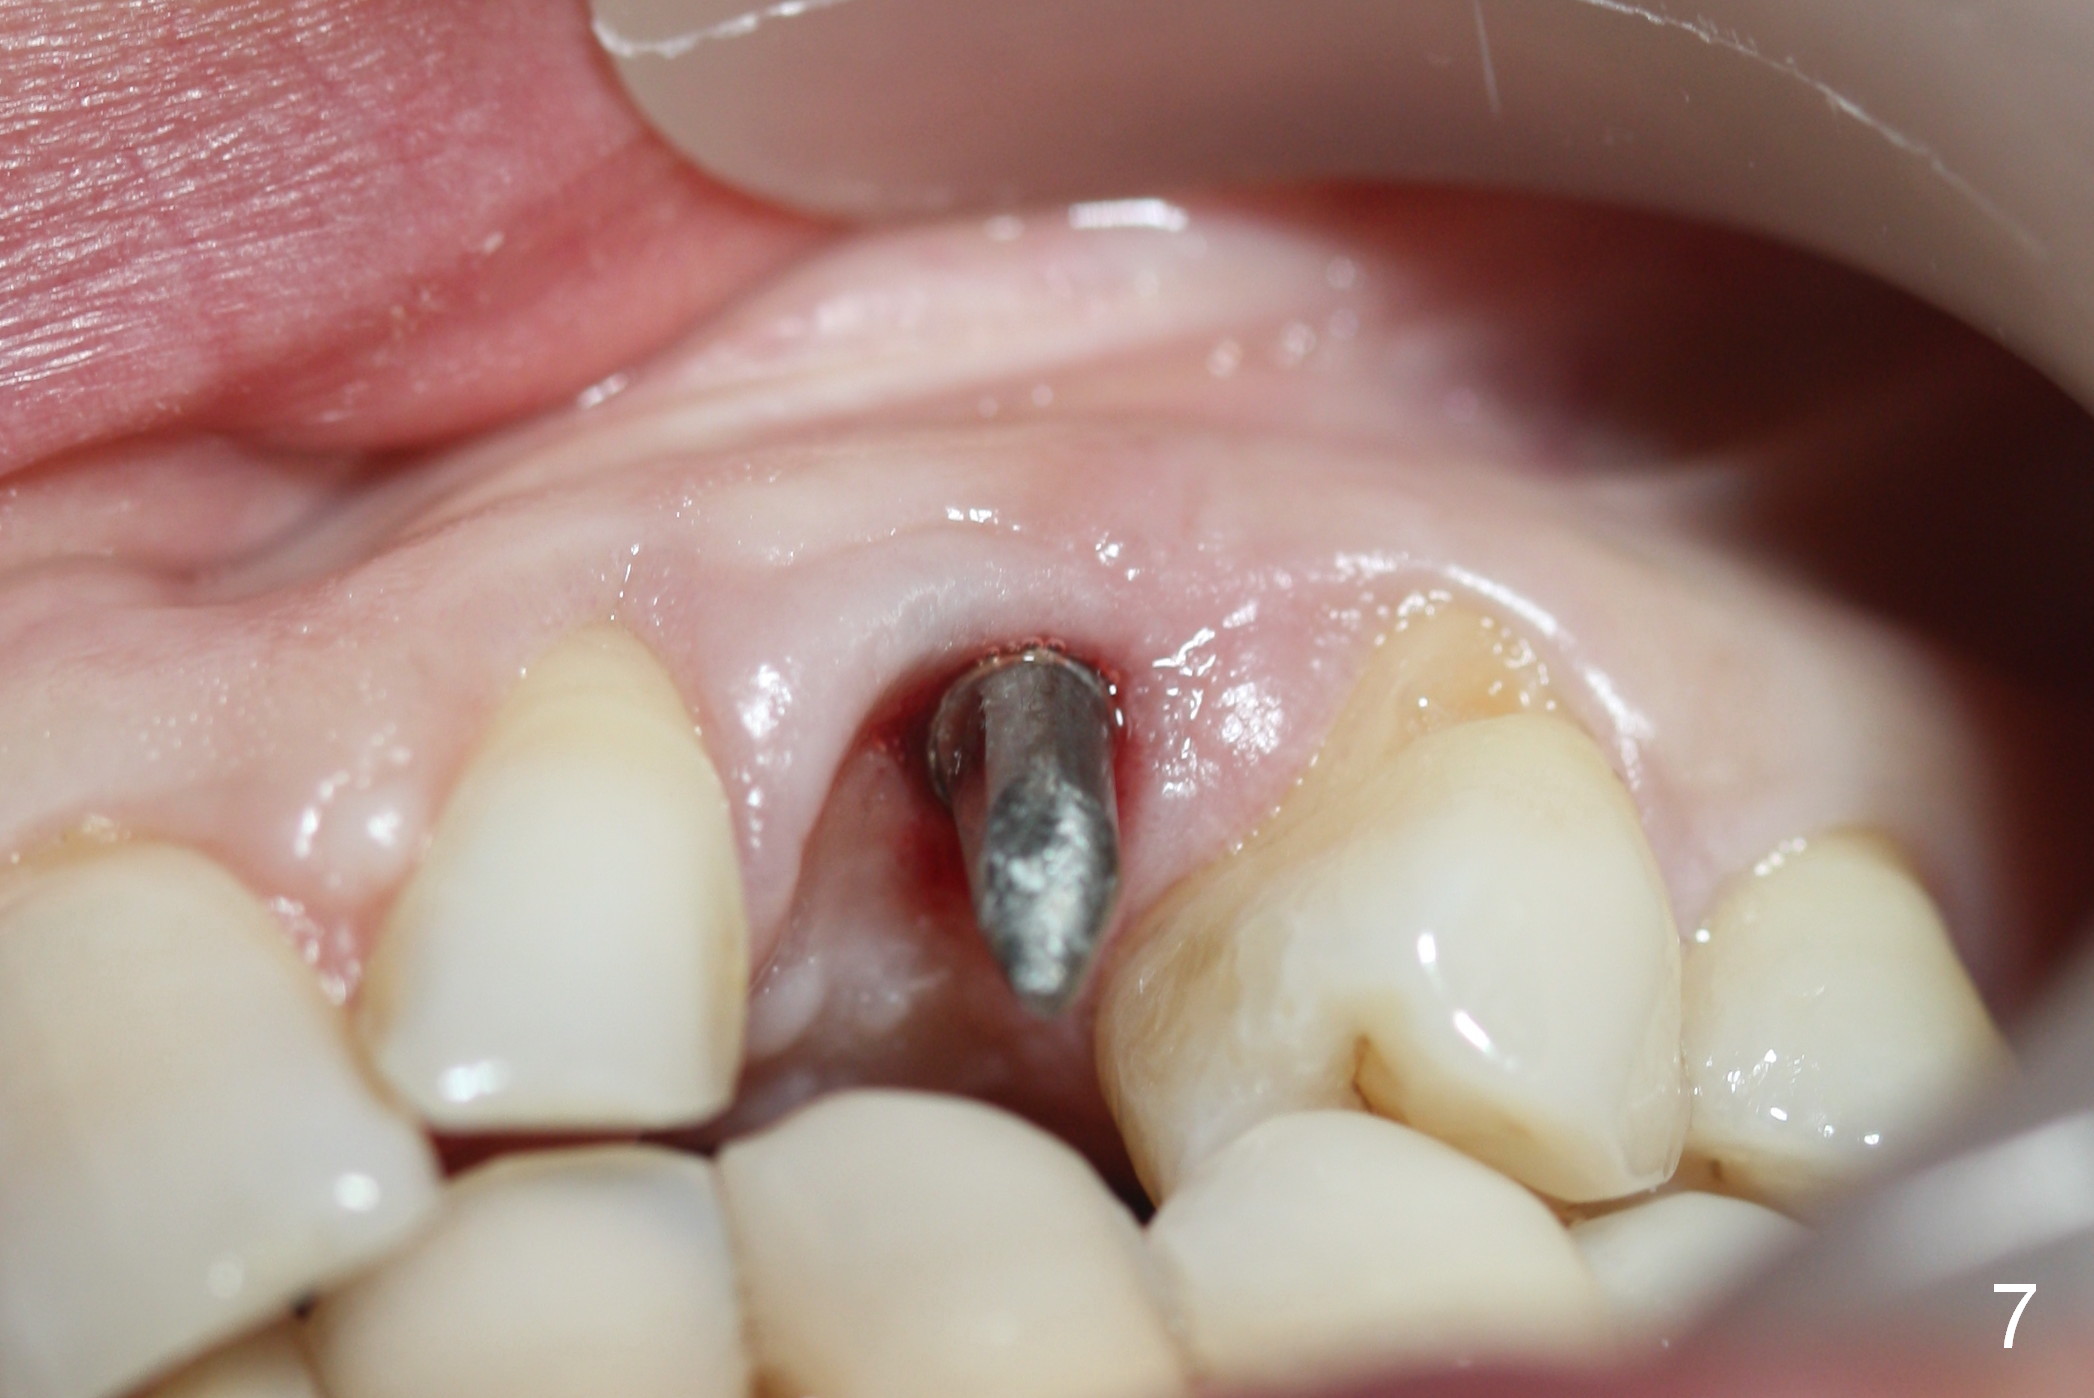

Eight months postop, the patient returns for #11 restoration. She reports no problem at #11, while there is light tenderness with a 2-piece implant (4.5x20 mm) at #6 at night (Fig.10, a portion of panoramic X-ray). Clinical exam reveals no abnormality at #6. Although the implant at #11 is buccally placed, there is no buccal plate atrophy (Fig.6,7). In fact the 20 mm 1-piece implant is placed in the bone (septum) between the nasal cavity (Fig.10 pink dashed line; Fig.13 (CBCT (52 year-old lady) N) and the maxillary sinus (yellow dashed line, S). In fact the apparent nasal floor indicated as arrowheads in Fig.2 and 10 is the horizontal plate of the palatine bone (hard palate)! Therefore there is no nasal floor perforation in this case. A long implant is indicated in the upper canine.

The main reason for the failure of this case is buccal placement of the implant (Fig.11 A: abutment). Every time an implant is placed at the upper anterior, make sure that palatal placement is done (Fig.12 *). The most critical step is the 1st pilot drill. If the position is not ideal, use a Lindemann bur for adjustment. Check repeatedly. If the implant starts to be deviated buccally, remove the implant, use the Lindemann bur to remove more of the palatal bone and place the implant palatally.